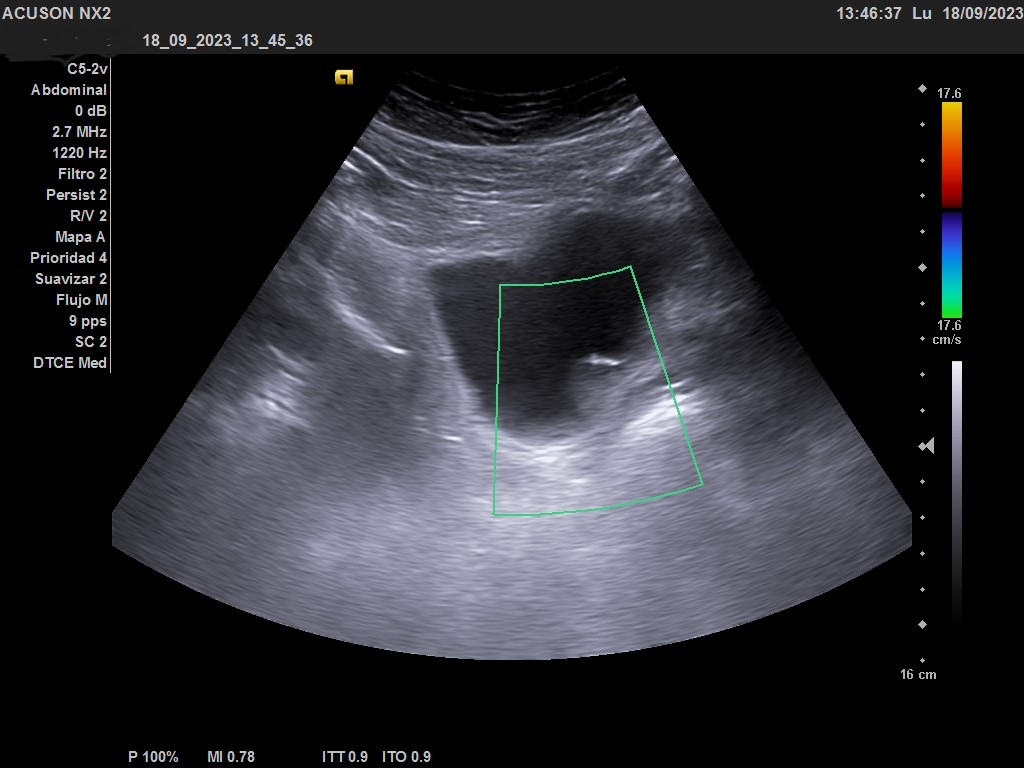

Hallazgos ecográficos

Ecografía clínica urológica: vejiga moderadamente replecionada. Se visualiza en pared posterior imagen hiperecogénica que no capta al Doppler color, de características sospechosas de malignidad. Riñones sin alteraciones en parénquima ni signos de hidronefrosis.

En la ecografía urológica reglada ambos riñones son de tamaño normal y parénquima conservado. La vejiga está replecionada, pero se identifica un engrosamiento nodular de 26 x 15 mm en la pared inferolateral izquierda, próxima al meato. Próstata de pequeño tamaño con un volumen de 7 cc.

Orientación diagnóstica de tumor vesical.